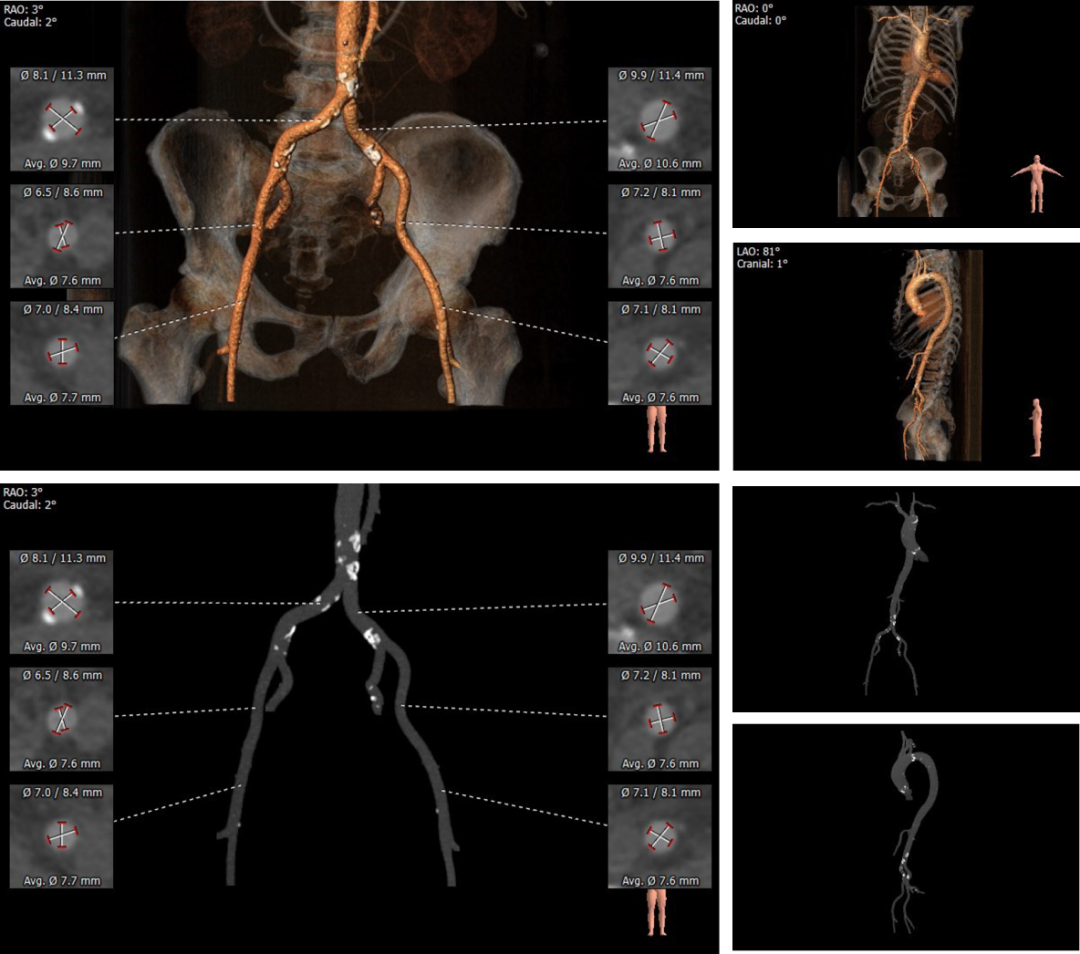

主动脉根部测量

瓣上评估

外周血管及主动脉弓解剖